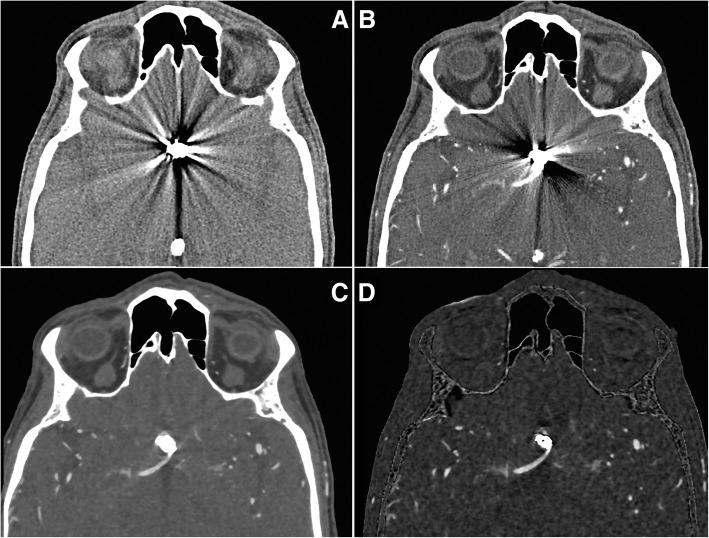

Fig. 1.

Impact of post-processing on image quality and metal artifact reduction. a Non-enhanced CT and b CT angiography with pronounced scattering artifacts of a coil-treated anterior communicating artery aneurysm. c CT angiography with metal artifact reduction (MAR) and model-based iterative reconstruction (MBIR) providing substantial artifact reduction. d Subtraction CT angiography with MAR and MBIR filtering providing further artifact reduction and resulting in adequate image quality for diagnostic evaluation